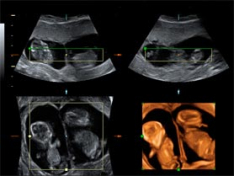

Ecografía de 12 semanas: Gemelos en dos bolsas

La ecografía en 3D de un embarazo gemelar muestra como los dos fetos crecen cada uno en una bolsa amniótica distinta, con su propia placenta. Los embarazos múltiples suelen conllevar más complicaciones que los embarazos únicos.

Gemelos de 12 semanas

La membrana de separación es claramente visible, más en la parte superior, donde se aprecia una cuña de tejido placentario (*). Esto indica que existen dos bolsas y dos placentas, la mejor situación para un embarazo gemelar. Cuantos más elementos comparten, más complicaciones puede tener la gestación.